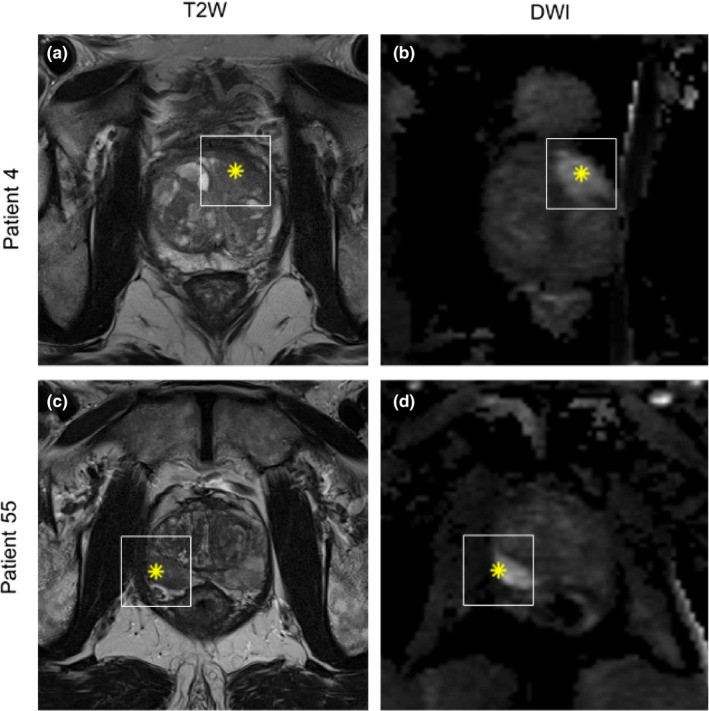

All analyses were done using Matlab 2017b. Heavy computations were performed in parallel on a local cluster with 20 workers (processing units) available. Axial T2W and DWI (b‐value = 800) image series were resampled to 0.5 mm × 0.5 mm and T2W series were z‐score normalized to account for interpatient intensity variation. Region of interest (ROI) was defined as a 2D image region of 61 × 61 pixels around the provided lesion coordinate. The size of the ROI was chosen large enough to ensure coverage of largest tumors but as tightly around the lesion as possible. Examples of the ROI around a lesion in AFS and in PZ in shown in Fig. 1. No image coregistration was performed as T2W and DWI series were not used together, and the image fragment of 61 × 61 pixels should ensure that the lesion is within the fragment even with some geometric distortion.

Figure 1.

Example of region of interest (white square) around lesion from patient 4 (a and b) with a lesion located in the anterior fibromuscular stroma and patient 55 (c and d) with a lesion in the peripheral zone. Left column is T2W and right column DWI sequence. Asterix inside region of interest denotes the point from where the prostate biopsy was obtained.